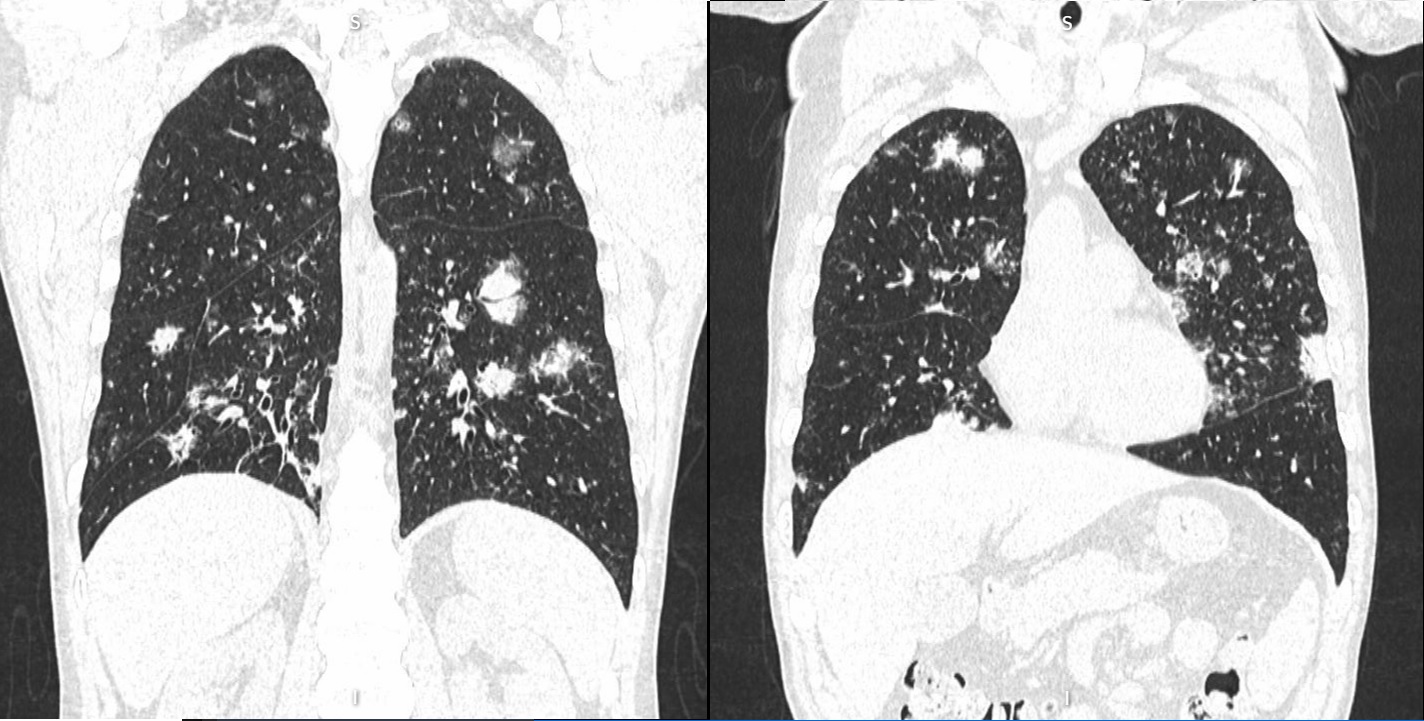

Introduction: This case report describes a serious complication of delayed human immunodeficiency virus (HIV) diagnosis in a patient initially misdiagnosed with palliative-stage cancer and subsequently diagnosed with B-cell lymphoma. This situation highlights the diagnostic challenges and treatment implications following HIV diagnosis, and underscores the critical importance of accurate and timely HIV detection in oncology patients.

Case presentation: A 39-year-old man was initially diagnosed with lung cancer based on computed tomography and histopathologic findings. He was treated with 2 lines of chemotherapy over an 8-month period, the neoplastic lung lesions progressed, and he was referred to palliative care. Two years after his initial diagnosis, during the management of an actively bleeding gastric tumor, he was diagnosed with HIV and referred to an infectious disease unit. Immediate antiretroviral treatment was initiated after diagnosis, and further evaluation confirmed the presence of B-cell lymphoma. A retrospective review suggested that the initial cancer diagnosis was likely misinterpreted and was in fact lymphoma, a malignancy commonly associated with HIV. Lymphoma treatment was initiated, and after 1 year, the patient achieved HIV-1 virologic suppression and near-complete remission of all lesions.